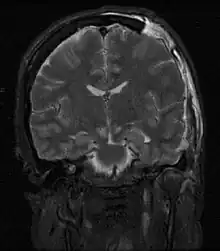

MRI showing injury due to brain herniation

MRI showing damage due to herniation. This patient was left with residual disabilities including those involving movement and speech.[16]

Treatment involves removal of the etiologic mass and decompressive craniectomy. Brain herniation can cause severe disability or death. In fact, when herniation is visible on a CT scan, the prognosis for a meaningful recovery of neurological function is poor.[2] The patient may become paralyzed on the same side as the lesion causing the pressure, or damage to parts of the brain caused by herniation may cause paralysis on the side opposite the lesion.[11] Damage to the midbrain, which contains the reticular activating network which regulates consciousness, will result in coma.[11] Damage to the cardio-respiratory centers in the medulla oblongata will cause respiratory arrest and (secondarily) cardiac arrest.[11] Investigation is underway regarding the use of neuroprotective agents during the prolonged post-traumatic period of brain hypersensitivity associated with the syndrome.[17]